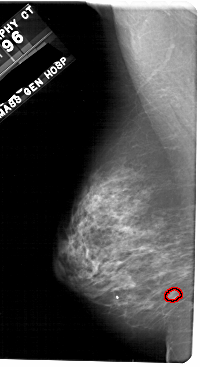

A_1709_1.LEFT_CC

LEFT_CC LINES 5341 PIXELS_PER_LINE 2806 BITS_PER_PIXEL 12 RESOLUTION 43.5 OVERLAY

FILE: A_1709_1.LEFT_CC.OVERLAY

TOTAL_ABNORMALITIES 1

ABNORMALITY 1

LESION_TYPE MASS SHAPE LOBULATED MARGINS CIRCUMSCRIBED

ASSESSMENT 4

SUBTLETY 2

PATHOLOGY BENIGN

TOTAL_OUTLINES 1

BOUNDARY